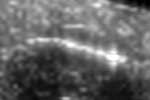

Coronary artery disease (CAD) is a cardiovascular condition with high morbidity and mortality. Intravascular optical coherence tomography (IVOCT) has been considered as an optimal imagining system for the diagnosis and treatment of CAD. Constrained by Nyquist theorem, dense sampling in IVOCT attains high resolving power to delineate cellular structures/ features. There is a trade-off between high spatial resolution and fast scanning rate for coronary imaging. In this paper, we propose a viable spectral-spatial acquisition method that down-scales the sampling process in both spectral and spatial domain while maintaining high quality in image reconstruction. The down-scaling schedule boosts data acquisition speed without any hardware modifications. Additionally, we propose a unified multi-scale reconstruction framework, namely Multiscale- Spectral-Spatial-Magnification Network (MSSMN), to resolve highly down-scaled (compressed) OCT images with flexible magnification factors. We incorporate the proposed methods into Spectral Domain OCT (SD-OCT) imaging of human coronary samples with clinical features such as stent and calcified lesions. Our experimental results demonstrate that spectral-spatial downscaled data can be better reconstructed than data that is downscaled solely in either spectral or spatial domain. Moreover, we observe better reconstruction performance using MSSMN than using existing reconstruction methods. Our acquisition method and multi-scale reconstruction framework, in combination, may allow faster SD-OCT inspection with high resolution during coronary intervention.